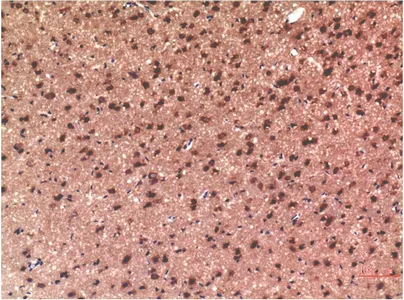

Tau(10E3)Mouse Monoclonal Antibody

Cat: AMM18659

Size1:50μl Price1:$118

Size2:100μl Price2:$220

Size3:500μl Price3:$980

Size2:100μl Price2:$220

Size3:500μl Price3:$980